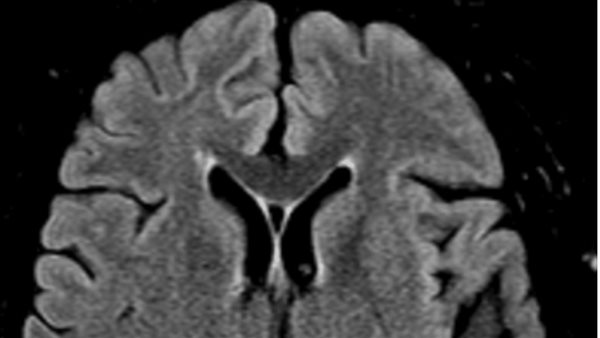

وأظهرت نتائج التحاليل المختبرية بعد العملية عدم وجود أي اضطرابات كبيرة، وأكد التصوير بالأشعة المقطعية للأوعية الدموية سلامة الأوعية الكبيرة من أي انسدادات، ما استبعد الحاجة إلى تدخلات ميكانيكية، أما التصوير بالرنين المغناطيسي فقد أظهر اعتلالًا وعائيًا دقيقًا مزمنًا، دون وجود علامات لسكتة دماغية حادة، وهو ما دفع الفريق الطبي للترجيح بأن السبب يعود إلى تأثيرات التخدير الإقليمي.